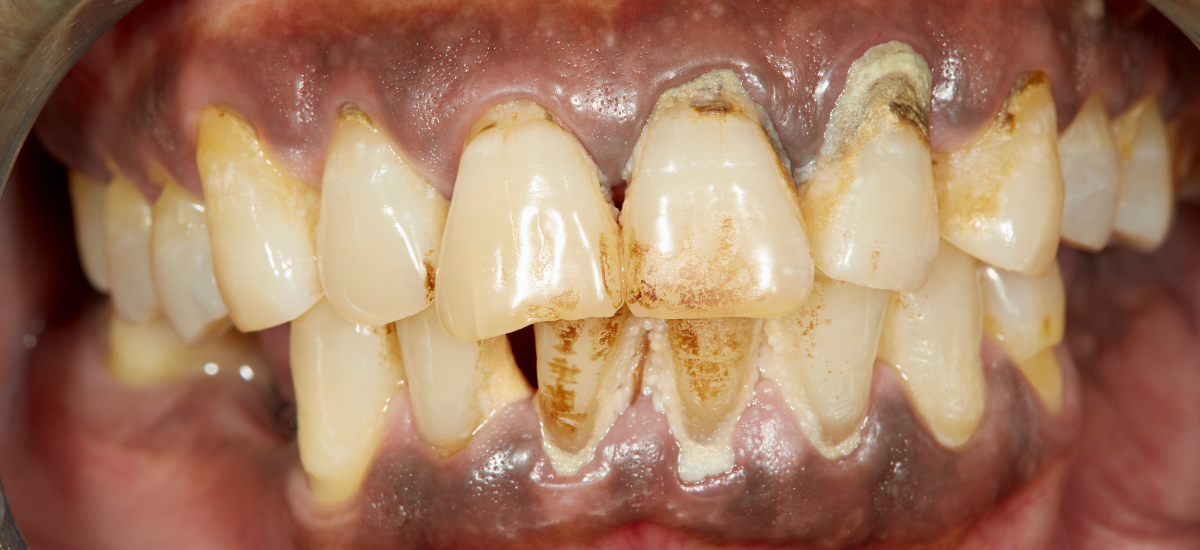

5. 重度歯周病は“見てわかる”段階に

・歯がグラつく・膿が出る状態とは

重度の歯周病は、その名のとおり歯ぐきや骨の状態が深刻な段階に入っています。ここまで進行すると、患者様自身でも明らかな異常に気づくケースがほとんどです。たとえば、「歯を指で押すと揺れる」「歯ぐきから膿のようなものが出てくる」「歯が長くなったように見える」といった症状は、すべて歯周病が深刻化しているサインです。特に歯がグラつく状態は、歯を支える歯槽骨が大きく吸収されていることを意味します。さらに進むと、食事のたびに痛みや違和感を覚えるようになり、生活の質にも大きな影響が出てしまいます。

・歯槽骨の吸収が進むと抜歯の可能性も

歯を支える土台となっている「歯槽骨」は、歯周病菌の感染により徐々に破壊されていきます。この骨が著しく減少すると、歯は自力で支えきれず、最終的には自然に抜け落ちるか、抜歯が必要になることもあります。重度歯周病の方の中には、「歯を抜かずに済ませたい」という想いでギリギリまで来院をためらってしまう方も多いですが、実際には早めの対処が歯を残すカギになります。歯の動揺度が高まることで、食事中の不便さだけでなく、発音のしづらさや自信喪失にもつながることがあるのです。